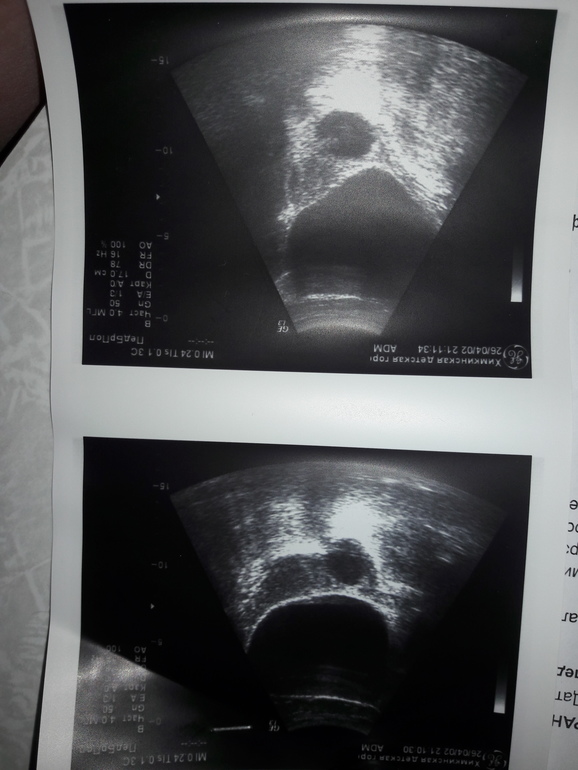

Добрый день, подскажите пожалуйста! У дочки 11 лет (07.05.2008гр) на узи обнаружили фоликулярную кисту правого яичника 30ммх35мм. Это очень опасно и что в данном случае делать? Хотелось бы знать, пока ищем в нашем городе детского гинеколога. Месячные у нее регулярные по 4-7 дней, цикл 30 дней